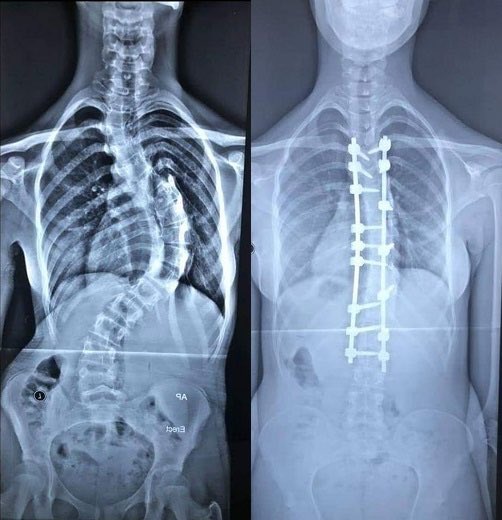

فتى عمره ١٥ يعيش بالسعودية وعائلته ضعيفة ماديًا يعاني من تحدب شديد بالعمود الفقري يستدعي إجراء عملية جراحية عاجلة لتعديل التحدب على كامل العمود الفقري حتى لايؤثر على الأعصاب مع عمل رقعة عظمية خارجية

هذي صور عشان تعرف وش معنى تحدب العمود الفقري .